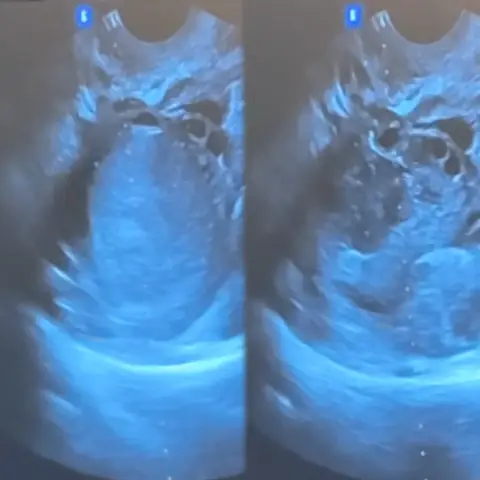

Live Ultrasound (Бодит хугацааны ЭХО)

"Уйланхай доторх шингэнийг соруулан авч,

бодит хугацаанд жижигсэж буй байдал"

Эмчилгээний явцад уйланхай устаж алга болж буйг

эмч өөрийн нүдээр баталгаажуулан хийдэг.